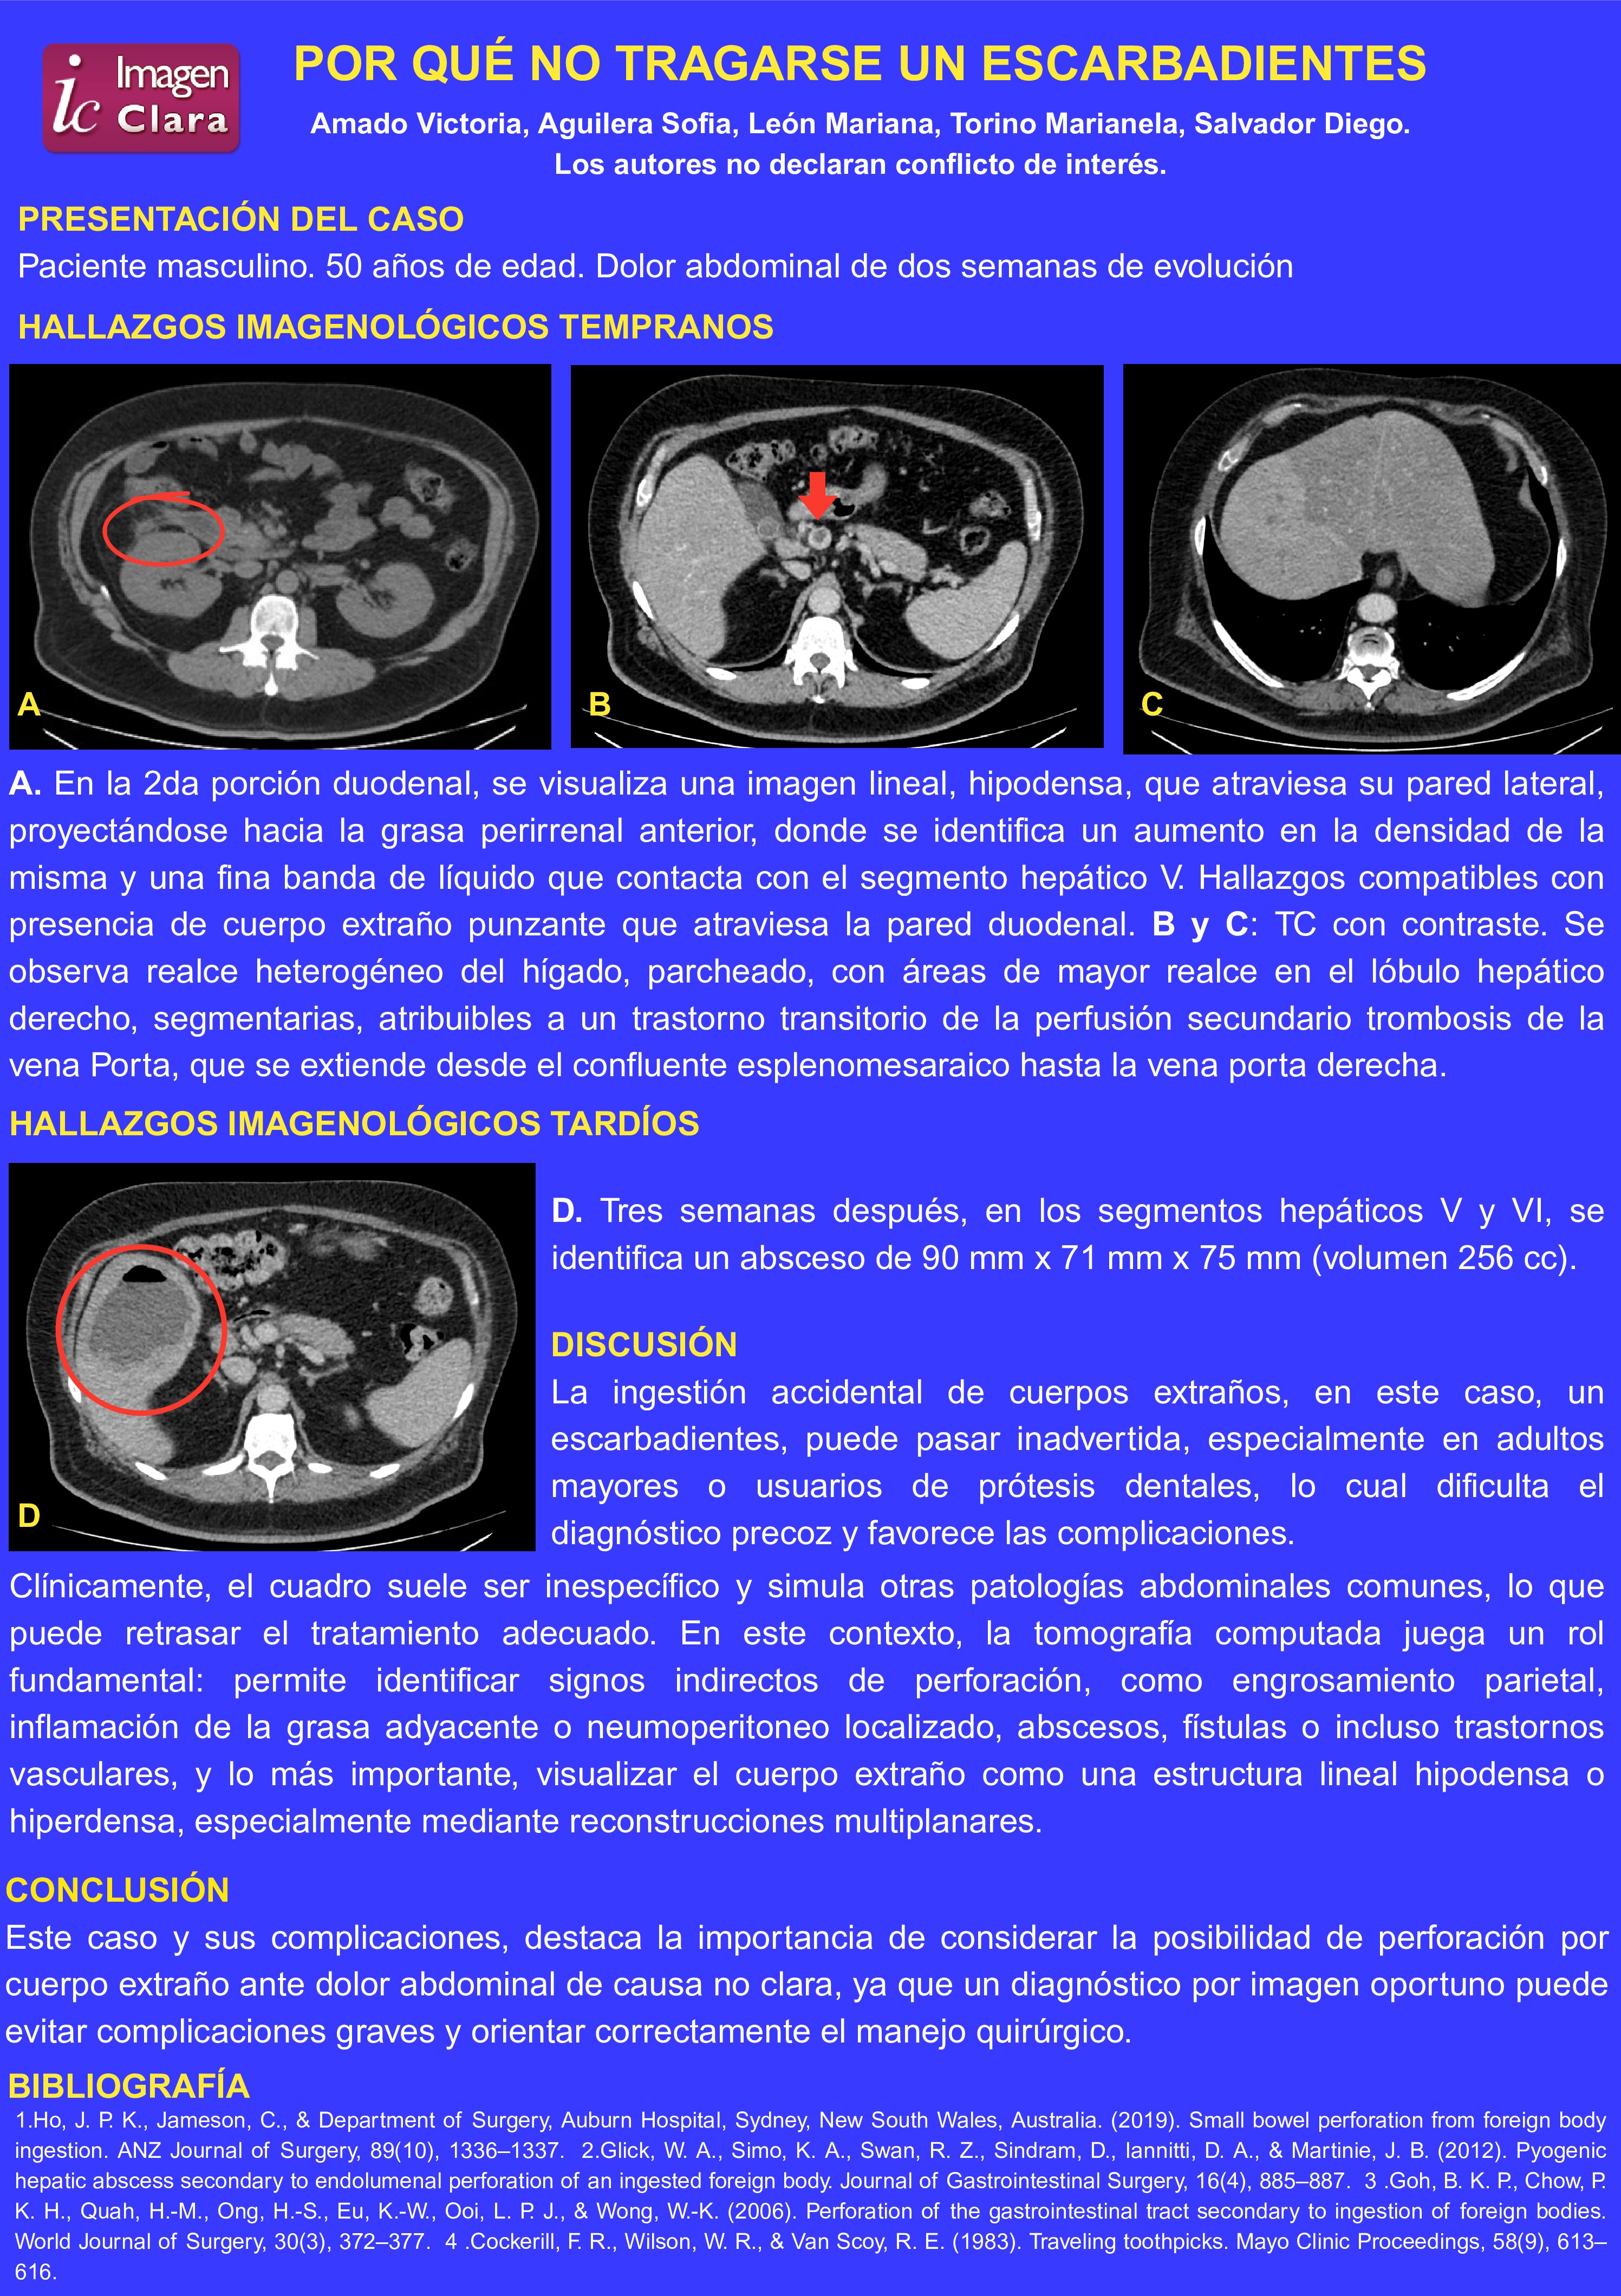

POR QUÉ NO TRAGARSE UN ESCARBADIENTES